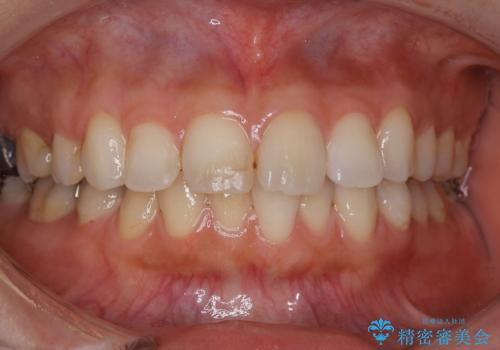

今回のような歯の移動量が大きい場合、インビザライン治療では歯が傾いてしまう場合があります。

また、かみ合わせが深い方の場合、インビザライン治療によってさらにかみ合わせが深くばってしまう場合があります。

ワイヤー治療では歯の傾きを抑えながら大きい距離の移動が可能で、かみ合わせが深くなるリスクも少ないです。

細かな動きはインビザライン治療の方が得意ですし、オープンバイト(開咬)と呼ばれる治療はかみ合わせを深くすることができるインビザラインの方が向いています。

それぞれの特性、得意な治療がありますので、患者様の状態に合わせた治療器具の選択が大事となります。